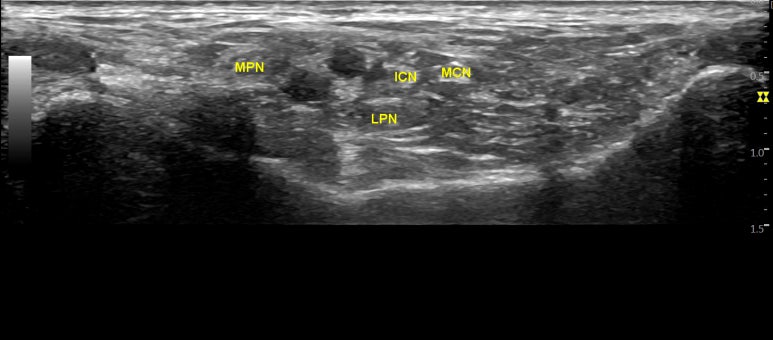

@ https://link.springer.com/chapter/10.1007/978-3-319-27482-9_75 발바닥의 감각은 대부분 후경골신경이 지배합니다. 후경골신경에서 갈라져나온 분지인 내측족저신경, 외측족저신경 내측종골신경, 하종골신경 4가지가 발바닥 감각의 95%를 지배하죠. 그러므로 한의학적 치료로 후경골신경을 조절하는 것이 발바닥통증,열감 치료의 핵심입니다. 환자분이 불편한 곳은 발바닥이지만 한의사가 치료할 곳은 발목이라는 의미이기도 합니다. > 발바닥이 화끈거리고 아픈 40대 환자 이제 치료 사례 설명 들어갑니다. 발바닥 통증, 열감으로 오신 49세 여자 환자분으로 양 발 모두 평발이셨어요. 식당 홀서빙하며 오래 서있는 일을 하시는데 도수치료와 체외충격파를 받아도 전혀 차도가 없어서 집에서 지압점을 찾아 누르고 핫팩 찜질을 하셨다고요. 증상이 점점 악화되자 같이 일하는 직원분이 바로한의원을 추천해줘서 오셨습니다. 문제가 되는 한의학의 대종, 수천혈을 진찰해보니 거골하관절(subtalar joint) 부근에서 찌릿한 티넬 사인(tinel sign)이 나타납니다.

초음파로 보는 알짜근육학 396p. 제가 출판한 초음파 전문서적 ## [초음파로 보는 알짜근육학]**을 보면

대종, 수천혈에는

후경골신경의 분지인 내/외측족저신경과

혈관이 지나가기 때문에

정확한 진단과

세밀한 침 치료를 위해

경혈 초음파가 반드시 필요합니다.